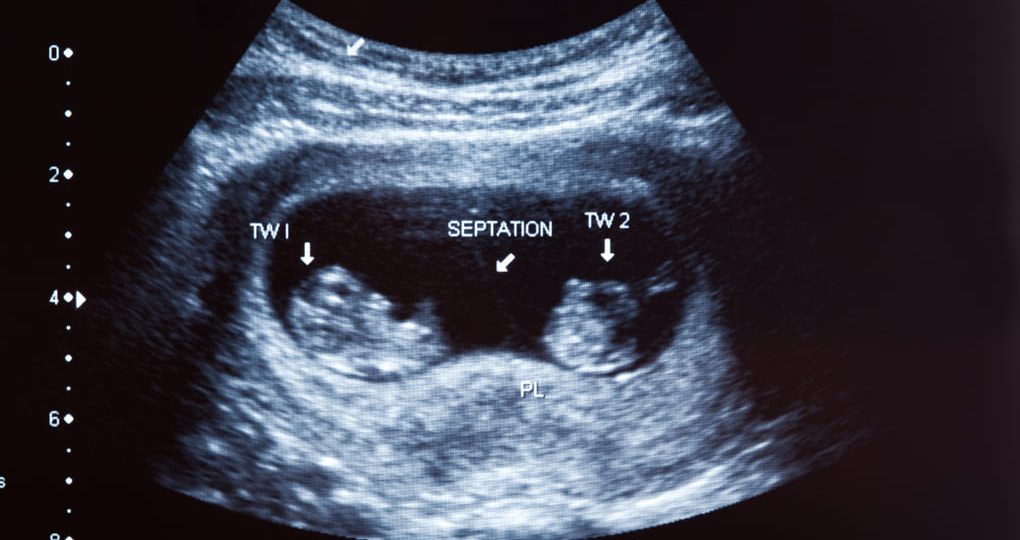

El deseo de tener gemelos ejerce un atractivo especial en muchas personas, ya que simboliza una experiencia singular que pocos padres pueden vivir en su existencia. Para individuos de Bolivia, esto puede tener una relevancia específica al examinar las alternativas disponibles. Aunque no existe una fórmula infalible para garantizar un embarazo múltiple, ciertos factores pueden incrementar las posibilidades.A continuación, explora cómo se producen los embarazos gemelares y qué opciones podrías considerar si deseas aumentar tus posibilidades.¿Qué implica tener un embarazo múltiple?Los embarazos múltiples se dividen principalmente en dos tipos: gemelos idénticos y mellizos. Los gemelos idénticos surgen cuando un único…